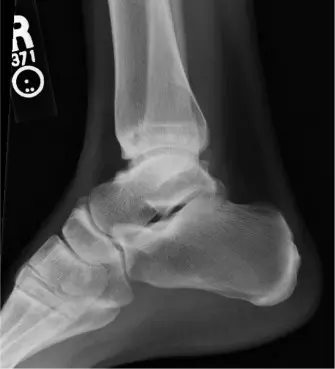

يمثل "كاحل راقصة الباليه" تحديًا طبيًا معقدًا، يتسم بألم مزمن، قيود وظيفية، وغالبًا ما يكون تنكسًا تدريجيًا ينجم عن المتطلبات الميكانيكية الحيوية الفريدة والقصوى التي يتعرض لها مفصل الكاحل. على عكس عامة السكان، تعرض راقصات الباليه كواحلهن بانتظام لنطاقات حركة تفوق الحدود الفسيولوجية الطبيعية، خاصة الانثناء الأخمصي القسري (وضع الوقوف على أطراف الأصابع "en pointe") والتحميل المتكرر للصدمات. هذا الإجهاد المستمر، سواء الجزئي أو الكلي، يجعل راقصات الباليه عرضة لطيف معين من الأمراض، بما في ذلك متلازمات الانحشار الأمامي والخلفي، الآفات الغضروفية العظمية في عظم الكاحل (OCLs)، عدم استقرار المفصل الظنبوبي الشظوي السفلي، التهاب الأوتار (الوتر الطويل المثني لإبهام القدم، الوتر الظنبوبي الخلفي)، وفي النهاية، خشونة الكاحل ما بعد الصدمة.

إن انتشار أمراض الكاحل بين راقصات الباليه المحترفات وشبه المحترفات مرتفع بشكل ملحوظ، حيث تشير الدراسات إلى أن 75-90% من الراقصات يعانين من آلام الكاحل المصاحبة للأعراض خلال مسيرتهن المهنية. وبينما تستجيب العديد من الحالات للعلاج غير الجراحي أو التدخل بالمنظار (مثل التنضير للانحشار أو الآفات الغضروفية العظمية)، فإن مجموعة فرعية من الراقصات تتطور لديهن خشونة الكاحل في مراحلها النهائية، على الرغم من الجهود المحافظة والجراحية السابقة المكثفة. يمثل هذا التطور تحديًا خاصًا في فئة سكانية يكون فيها الحفاظ على الحركة والإنتاج الوظيفي العالي أمرًا بالغ الأهمية لمهنتهن وجودة حياتهن.

لقد برز مفصل الكاحل الصناعي الكلي (Total Ankle Arthroplasty - TAA) كخيار علاجي قابل للتطبيق لخشونة الكاحل في مراحلها النهائية، حيث يوفر ميزة نظرية تتمثل في الحفاظ على الحركة مقارنةً بتثبيت مفصل الكاحل. ومع ذلك، لا يزال تطبيق مفصل الكاحل الصناعي في الفئة الرياضية، وتحديداً في راقصات الباليه، موضوع نقاش كبير ويتطلب اختيارًا دقيقًا للمرضى. تدور المخاوف حول بقاء الغرسة، وتآكل البولي إيثيلين، والنتائج الوظيفية في مواجهة تحميل المفصل الشديد ومتطلبات نطاق الحركة.